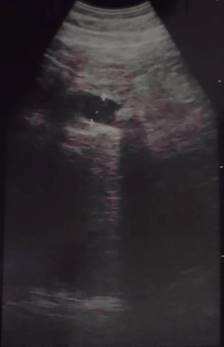

Masculino de 64 años, quien inicia su padecimiento con ictericia, negando otra sintomatología, llama la atención que se manifesta durante al menos tres días previos a su llegada a urgencias, su exploración física sin alteraciones, los laboratorios revelan una bilirrubina total de 25 mg/dl, bilirrubina directa de 22 mg/dl, fosfatasa alcalina 235 UI/l, gamma-glutamil transferasa 157 UI/l, creatinina 2.5 mg/dl, el resto de los laboratorios normales, se le realiza un ultrasonido de abdomen que reporta vesícula biliar mal definida, y dilatación de la vía biliar de 19 mm (Figura 1), se observa lito en colédoco de alrededor de 12 mm. Se integra el diagnóstico de coledocolitiasis, no obstante, se solicitan marcadores tumorales, con reporte de CA 19-9 de +8,000 UI; se solicita colangiorresonancia, la cual evidencia dilatación de vía biliar (vb) de 20 mm, lito de 16 mm a nivel del ámpula, no se reporta morfología de la vesícula biliar (VB), paciente candidato a colangiopancreatografía retrógrada endoscópica (CPRE) según el servicio de Gastroenterología. Se le realiza CPRE sin poder extraer lito, se programa para colecistectomía con exploración de vía biliar, el transoperatorio revela biliperitoneo, lisis de VB, fístula colecistocoledociana (Figura 2), litio único de 15 mm, se coloca sonda T, no se cuenta con servicio de cirugía hepatopancreatobiliar, por lo que no se realiza reparación definitiva, colangiografía transoperatoria revela paso de material de contraste a duodeno, sin fugas aparentes por orificio fistuloso (Figura 3), evolución posoperatoria favorable, el drenaje por sonda T en promedio 500 ml por día con disminución progresiva, con mejoría de hiperazoemia, con flujo urinario mayor a 0.5 ml/kg/h, colangiografía posoperatoria sin fugas, paso de medio de contraste a duodeno, reporte de patología revela adenocarcinoma de vesícula moderadamente diferenciado con infiltración a muscular (Figura 4). El paciente rechaza tratamiento médico y decide egreso voluntario, comprende y acepta los riesgos, no contamos con seguimiento a largo plazo.

Figura 2: Se observa el cuello pinzado y el orificio fistuloso en el conducto hepático común, además puede observarse la ausencia de vesícula biliar, dicho remanente se envió a patología.

Figura 3: Colangiografía transoperatoria que revela paso de material desde ambos conductos hepáticos hacia duodeno (pliegues semicirculares). Se observa fuga, la cual se manejó con drenaje aspirativo blando.